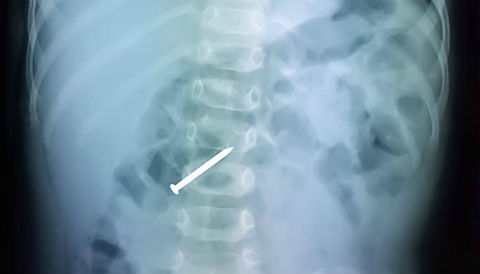

Thanh niên mang con dao cắm sâu ở lưng vào phòng mổ

10 phút sau khi bị con dao găm vào lưng, người đàn ông được đưa vào bệnh viện cấp cứu. Kết quả chụp X-quang, lưỡi dao đi vào vùng cột sống ngực, nằm chồng lên bóng tim.